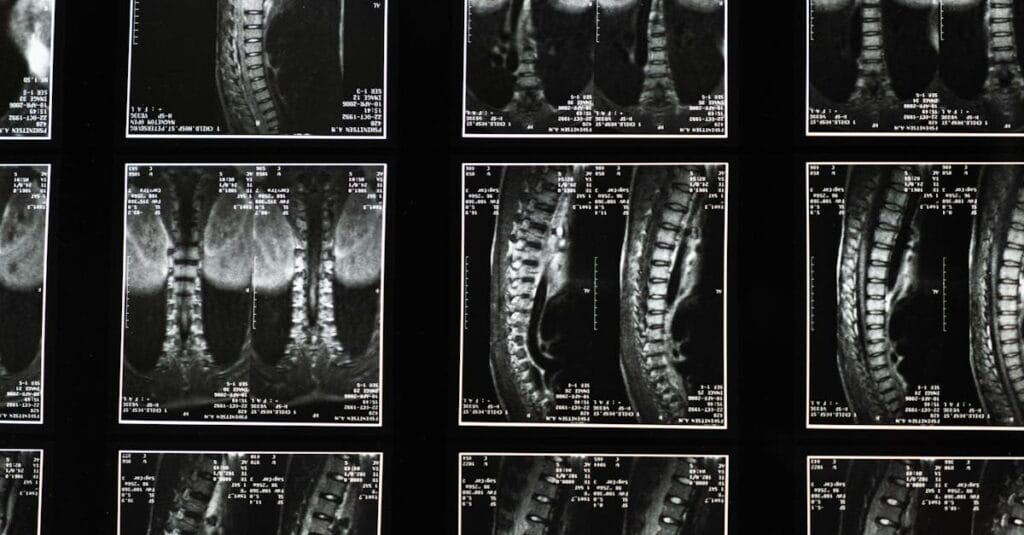

Avant d’entamer un traitement par décompression vertébrale, il est vital de réaliser une évaluation complète pour déterminer la gravité de la sténose et d’autres conditions sous-jacentes. Des examens d’imagerie, tels que des IRM ou des radiographies, peuvent être nécessaires pour visualiser l’état de la colonne vertébrale. En complément, la physiothérapie peut être recommandée pour renforcer les muscles du dos et améliorer la flexibilité.